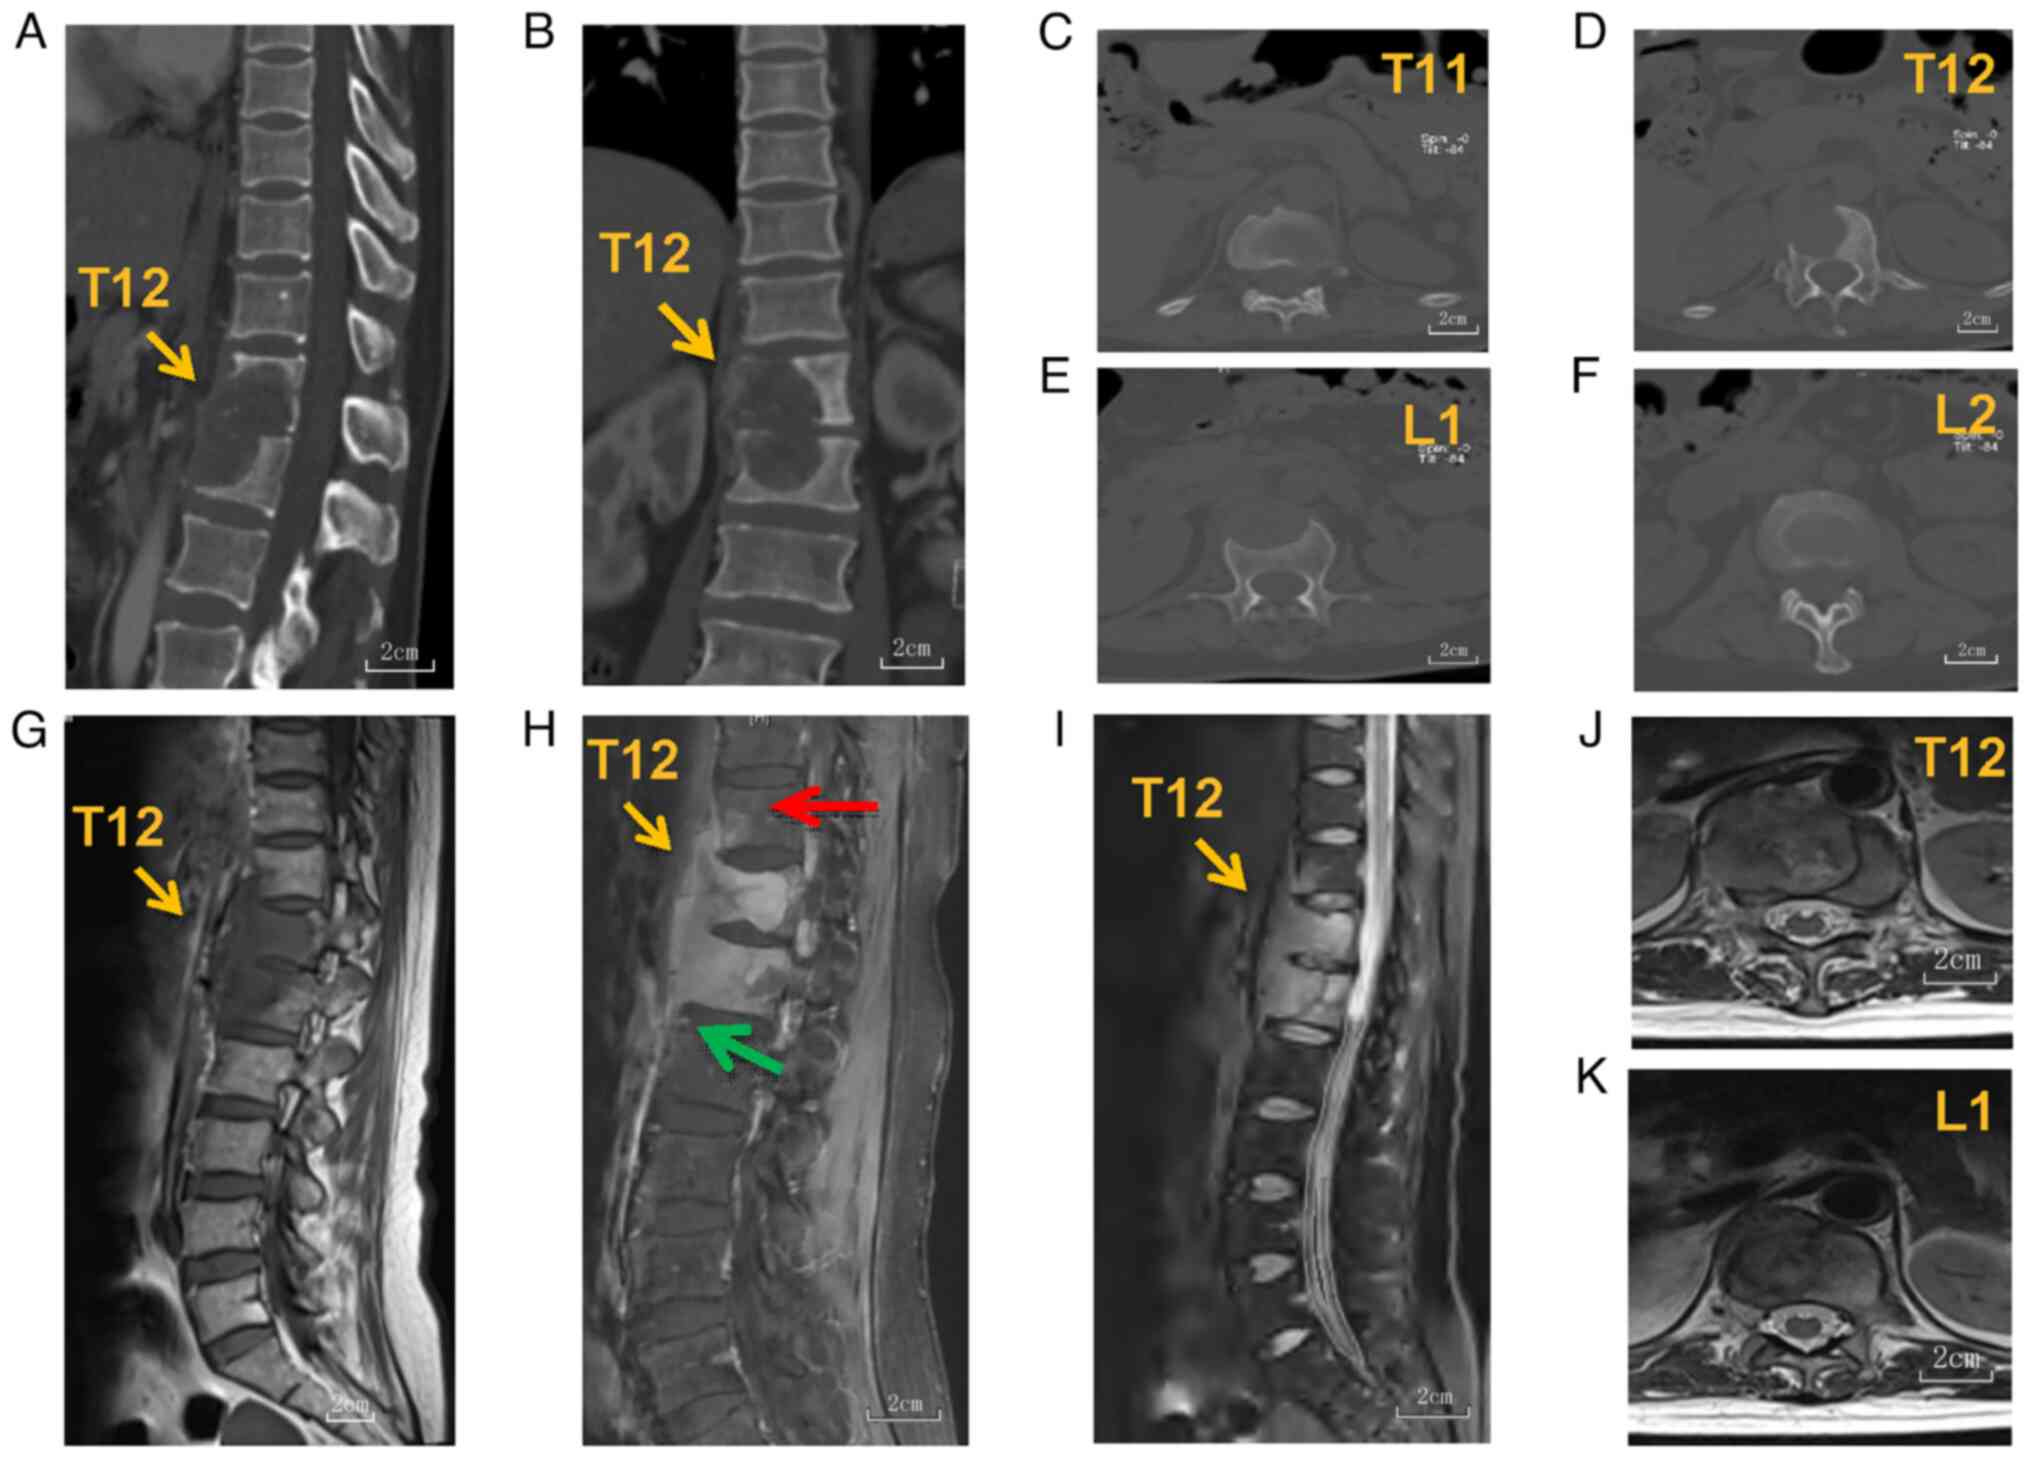

Spinal rhabdomyosarcoma (RMS) is a rare yet highly malignant tumor in adults. Literature on this entity is lacking and no mature treatment guideline is currently available. The treatment arsenals include surgery, radiotherapy and chemotherapy, being used singly or jointly. However, the prognosis is dismal, with a mean overall survival period of 10 months. Thus, any case of this disease with encouraging outcomes shall be shared. A case of a middle‑aged female patient with spinal RMS was presented in the current report. The patient suffered from back pain but was neurologically intact. The patient underwent a total en‑bloc spondylectomy of the T11‑L2 vertebrae and spinal reconstruction with 3D‑printed prosthetic vertebrae. Afterwards, the patient received a rigid schedule of stereotactic body radiotherapy (SBRT) and chemotherapy. To date, the patient has survived for 40 months, with the preservation of neurological function and sustained mitigation of local pain after the operation. The patient suffered subcutaneous colonization of tumor cells and pulmonary metastasis 10 months postoperatively, but obtained a long locoregional control of 19 months. In conclusion, total en‑bloc lesion resection is indicated for the treatment of isolated, primary spinal RMS in adults. Some authors reported that the usage of new surgical tools and instruments has facilitated surgery, which was previously invasive and technically challenging. Advanced radiotherapy techniques, such as SBRT, which were proven effective for local lesion control, should be implemented early after the operation. Chemotherapy remains the mainstay of treatment, but further research and evidence for the efficacy of regimens specifically for adults are required.

Figure 1